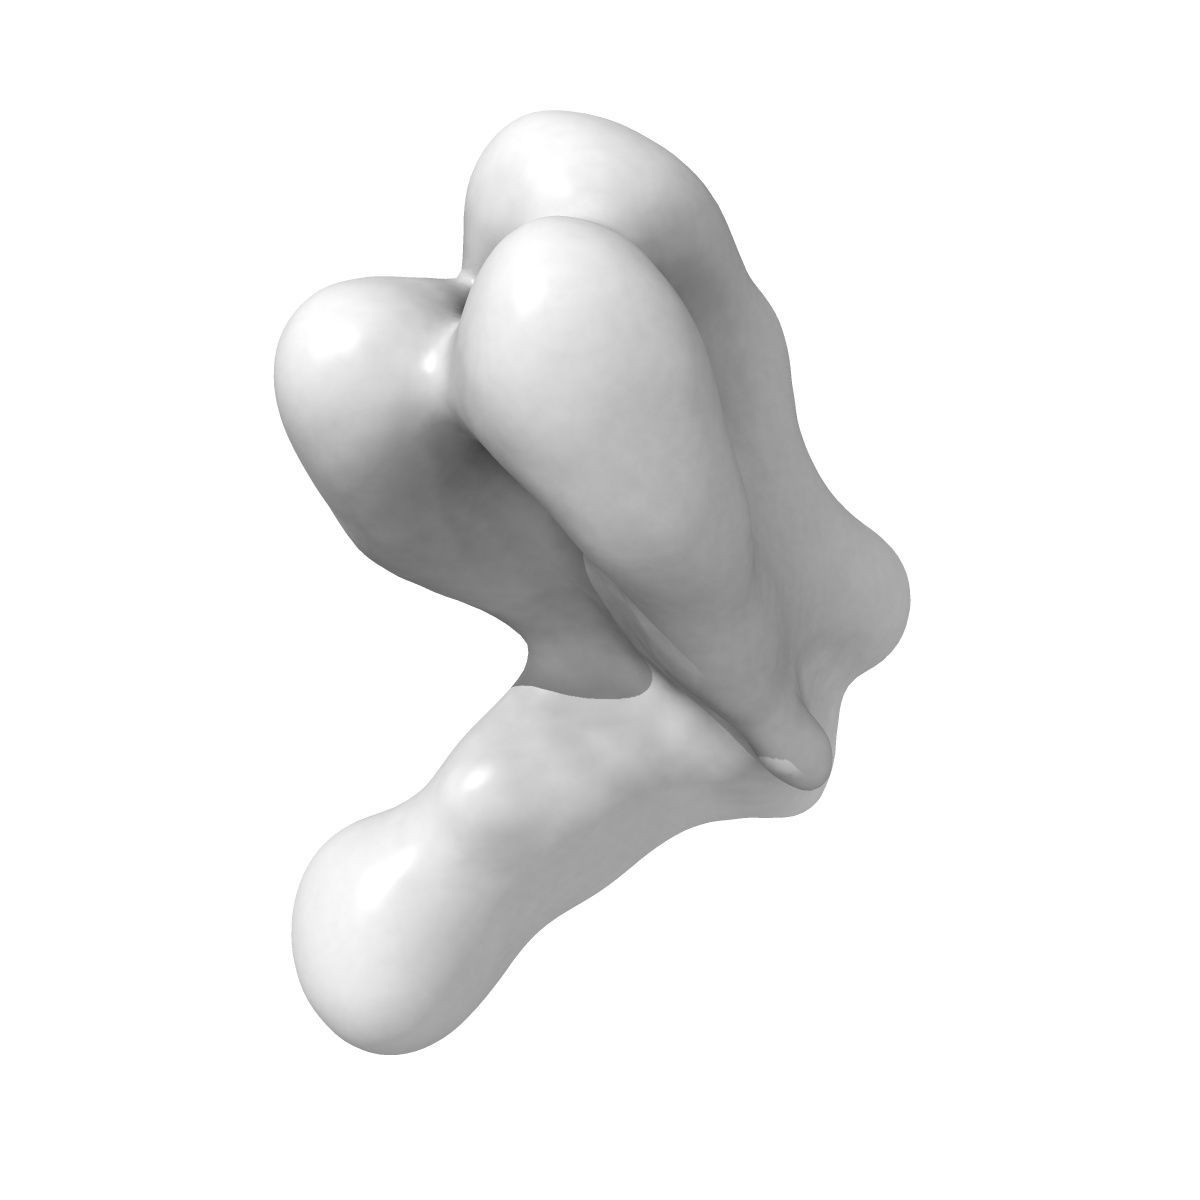

nsEM map of NHP RKd19wk30 polyclonal Fab in complex with H1 Cali09

Single-particle26.0 Å

Sample: nsEM map of NHP RKd19wk30 polyclonal Fab in complex with H1 Cali09